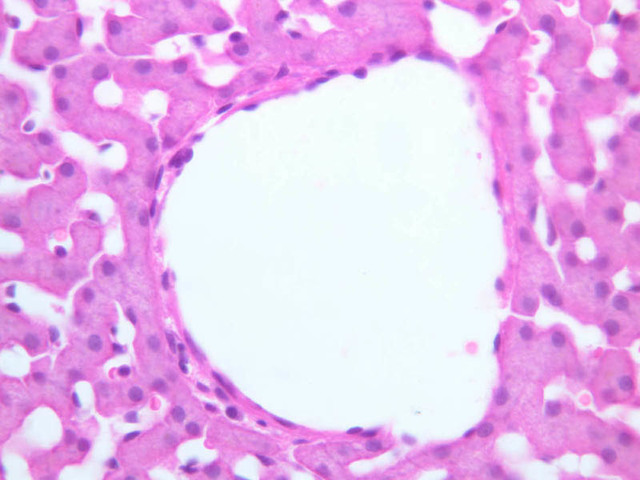

Examine the H&E-stained sections of liver (slides B-29 [10x, 20x, 40x-labeled] [2.5x-labeled, 10x, 20x, 40x] [10x-labeled, 20x, 40x-labeled] and B-30 [2.5x, 10x-labeled, 20x]). At low power, identify the connective tissue capsule (Glisson’s capsule), central veins and portal triads (portal canals). Note that the cells of the liver parenchyma (hepatocytes) appear as cords--more accurately, plates--of cells that radiate out from the central veins and partially enclose blood spaces known as hepatic sinusoids. Note that the plates of hepatocytes appear to branch and fuse and that, as a rule, they are only one or two cells thick. Do you see any binucleate hepatocytes?

Using the 10X (B-29, B-30)and 40X (B-29) objectives, examine several portal triads, noting the variable number of profiles of hepatic artery, portal vein and bile duct that comprise the portal triad. Near the boundary between adjacent lobules, try to find some of the small elements of the bile duct system known as canals of Hering.

Using the high dry objective, study the lining of the central vein and hepatic sinusoids (B-29). In some places the hepatocytes are exposed directly to the sinusoidal lumen, but, as a rule, there is a basal lamina which supports a discontinuous mosaic of endothelial cells and specialized phagocytic cells known as Kupffer cells. Find examples of Kupffer cells and endothelial cell nuclei. Note that in some places you may see a narrow space (the space of Disse) between hepatocytes and the basement membrane underlying endothelial and Kupffer cells. Using the oil immersion (100X) objective, look very carefully along the boundaries between adjacent hepatocytes to see if you can find a bile canaliculus--the most delicate portion of the bile duct system--the walls of which are formed by the plasma membranes of adjacent hepatocytes.

(3) A liver acinus is roughly elliptical in section. Its shorter axis (equator) is defined by the terminal branches of the hepatic artery and portal vein, which course along the boundary between adjacent classic lobules; its longer axis is defined by the two central veins nearest the equator (B-29). Although it is more difficult to visualize a liver acinus than a classic or portal lobule, the concept of acinar organization is very useful because certain features of liver metabolism best fit the acinar model.